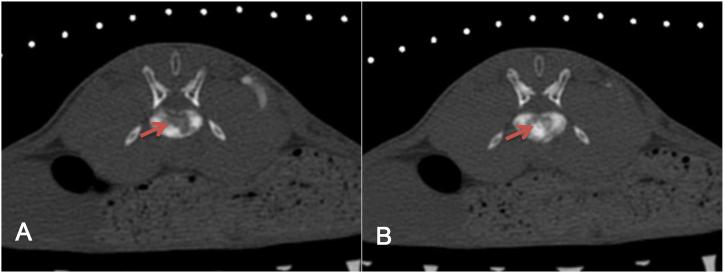

Thirty healthy New Zealand rabbits were randomly allocated to tissue suspension group and tumor block group, with 15 rabbits for each group. The VX2 tumor block and mixed suspension were inoculated into the L5 vertebral body under CT-guided percutaneous puncture. The PET/CT, MRI and CT examinations were performed at 7, 14 and 21 days after implantation. Fisher exact probability test was used to compare the success rate of the two implantation methods and the tumor display rate at each time point of the three examination methods. Observe the paralysis of tumor-forming rabbits, and immediately perform MWA/PVP/MWA + PVP treatment according to groups after paralysis to verify the safety and feasibility of treatment.

A total of 18 experimental rabbits were successfully modeled in two groups, of which the success rate was 26.6% (4/15) in tissue suspension group and 93.3% (14/15) in tumor block group, with statistically significant differences between two groups (P < 0.01). The tumor display rates by PET/CT, MRI and CT at each time point after implantation were: 83.3% (15/18), 16.6% (3/18), and 0% (0/18) at 7 days after implantation; 100% (18/18), 88.8% (16/18), and 11.1% (2/18) at 14 days after implantation; and 100% (18/18), 100% (18/18), 77.7% (14/18) at 21 days after implantation. The average paralysis time of 18 experimental rabbits successfully modeled was 24.44 ± 2.38 days, and MWA/PVP/MWA + PVP treatment was performed in groups immediately after paralysis. Except for 2 rabbits who died due to anesthesia overdose during anesthesia before treatment, the remaining 16 rabbits were successfully treated with MWA/PVP/MWA + PVP, and the technical success rate was 100% (16/16). In MWA group, one experimental rabbit was randomly selected and killed after ablation, and histopathological examination (H and E staining) was performed together with 2 experimental rabbits who died of anesthesia. The pathological changes before and after ablation were compared. The survival time of the remaining 15 experimental rabbits varied from 3 to 8 days after treatment.

The success rate of establishing rabbit vertebral tumor model by injecting tumor masses under the CT-guided percutaneous puncture is high, and the following MWA and PVP treatment can be successfully conducted. PET/CT is the most sensitive method for early detection of tumor compared with MRI and CT. Spectral Presaturation with Inversion Recovery (SPIR) sequence can significantly improve the detection rate of smaller tumors by MRI and shorten the detection time.